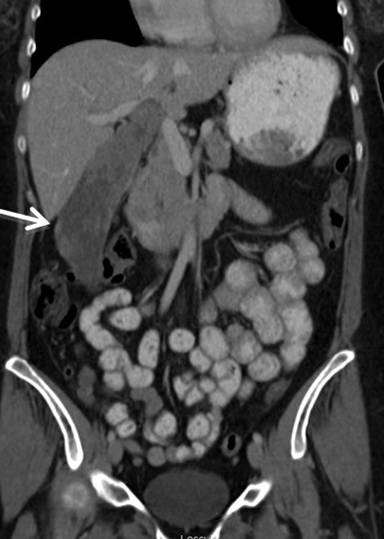

A Fifty nine-year-old otherwise healthy Caucasian female presented to an outside hospital in November 2010 with right upper quadrant pain and an enlarged gallbladder on ultrasound. She was taken to the operating room where the planned laparoscopic cholecystectomy was aborted given the identification of a segment 6 liver lesions. Biopsy demonstrated metastatic adenocarcinoma with a suspected gallbladder primary. Computerized tomography (CT) scan showed a giant gallbladder measuring about 18 cm (Figure 1). A large mass (11.0x3.1 cm) was visualized within the gallbladder with no clear evidence of invasion into liver, cystic duct or proximal common bile duct. Two hypodense, right lobe liver lesions were also present with the dominant mass measuring 2.5x1.8 cm in segment 6 (Figure 2). Preoperative tumor markers including cancer antigen 19-9 (CA 19-9) and carcinoembryonic antigen (CEA) were normal.

Figure 1. Preoperative CT scan demonstrating giant gallbladder. |